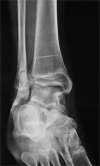

Figure 2

Anteroposterior X-ray of the ankle.